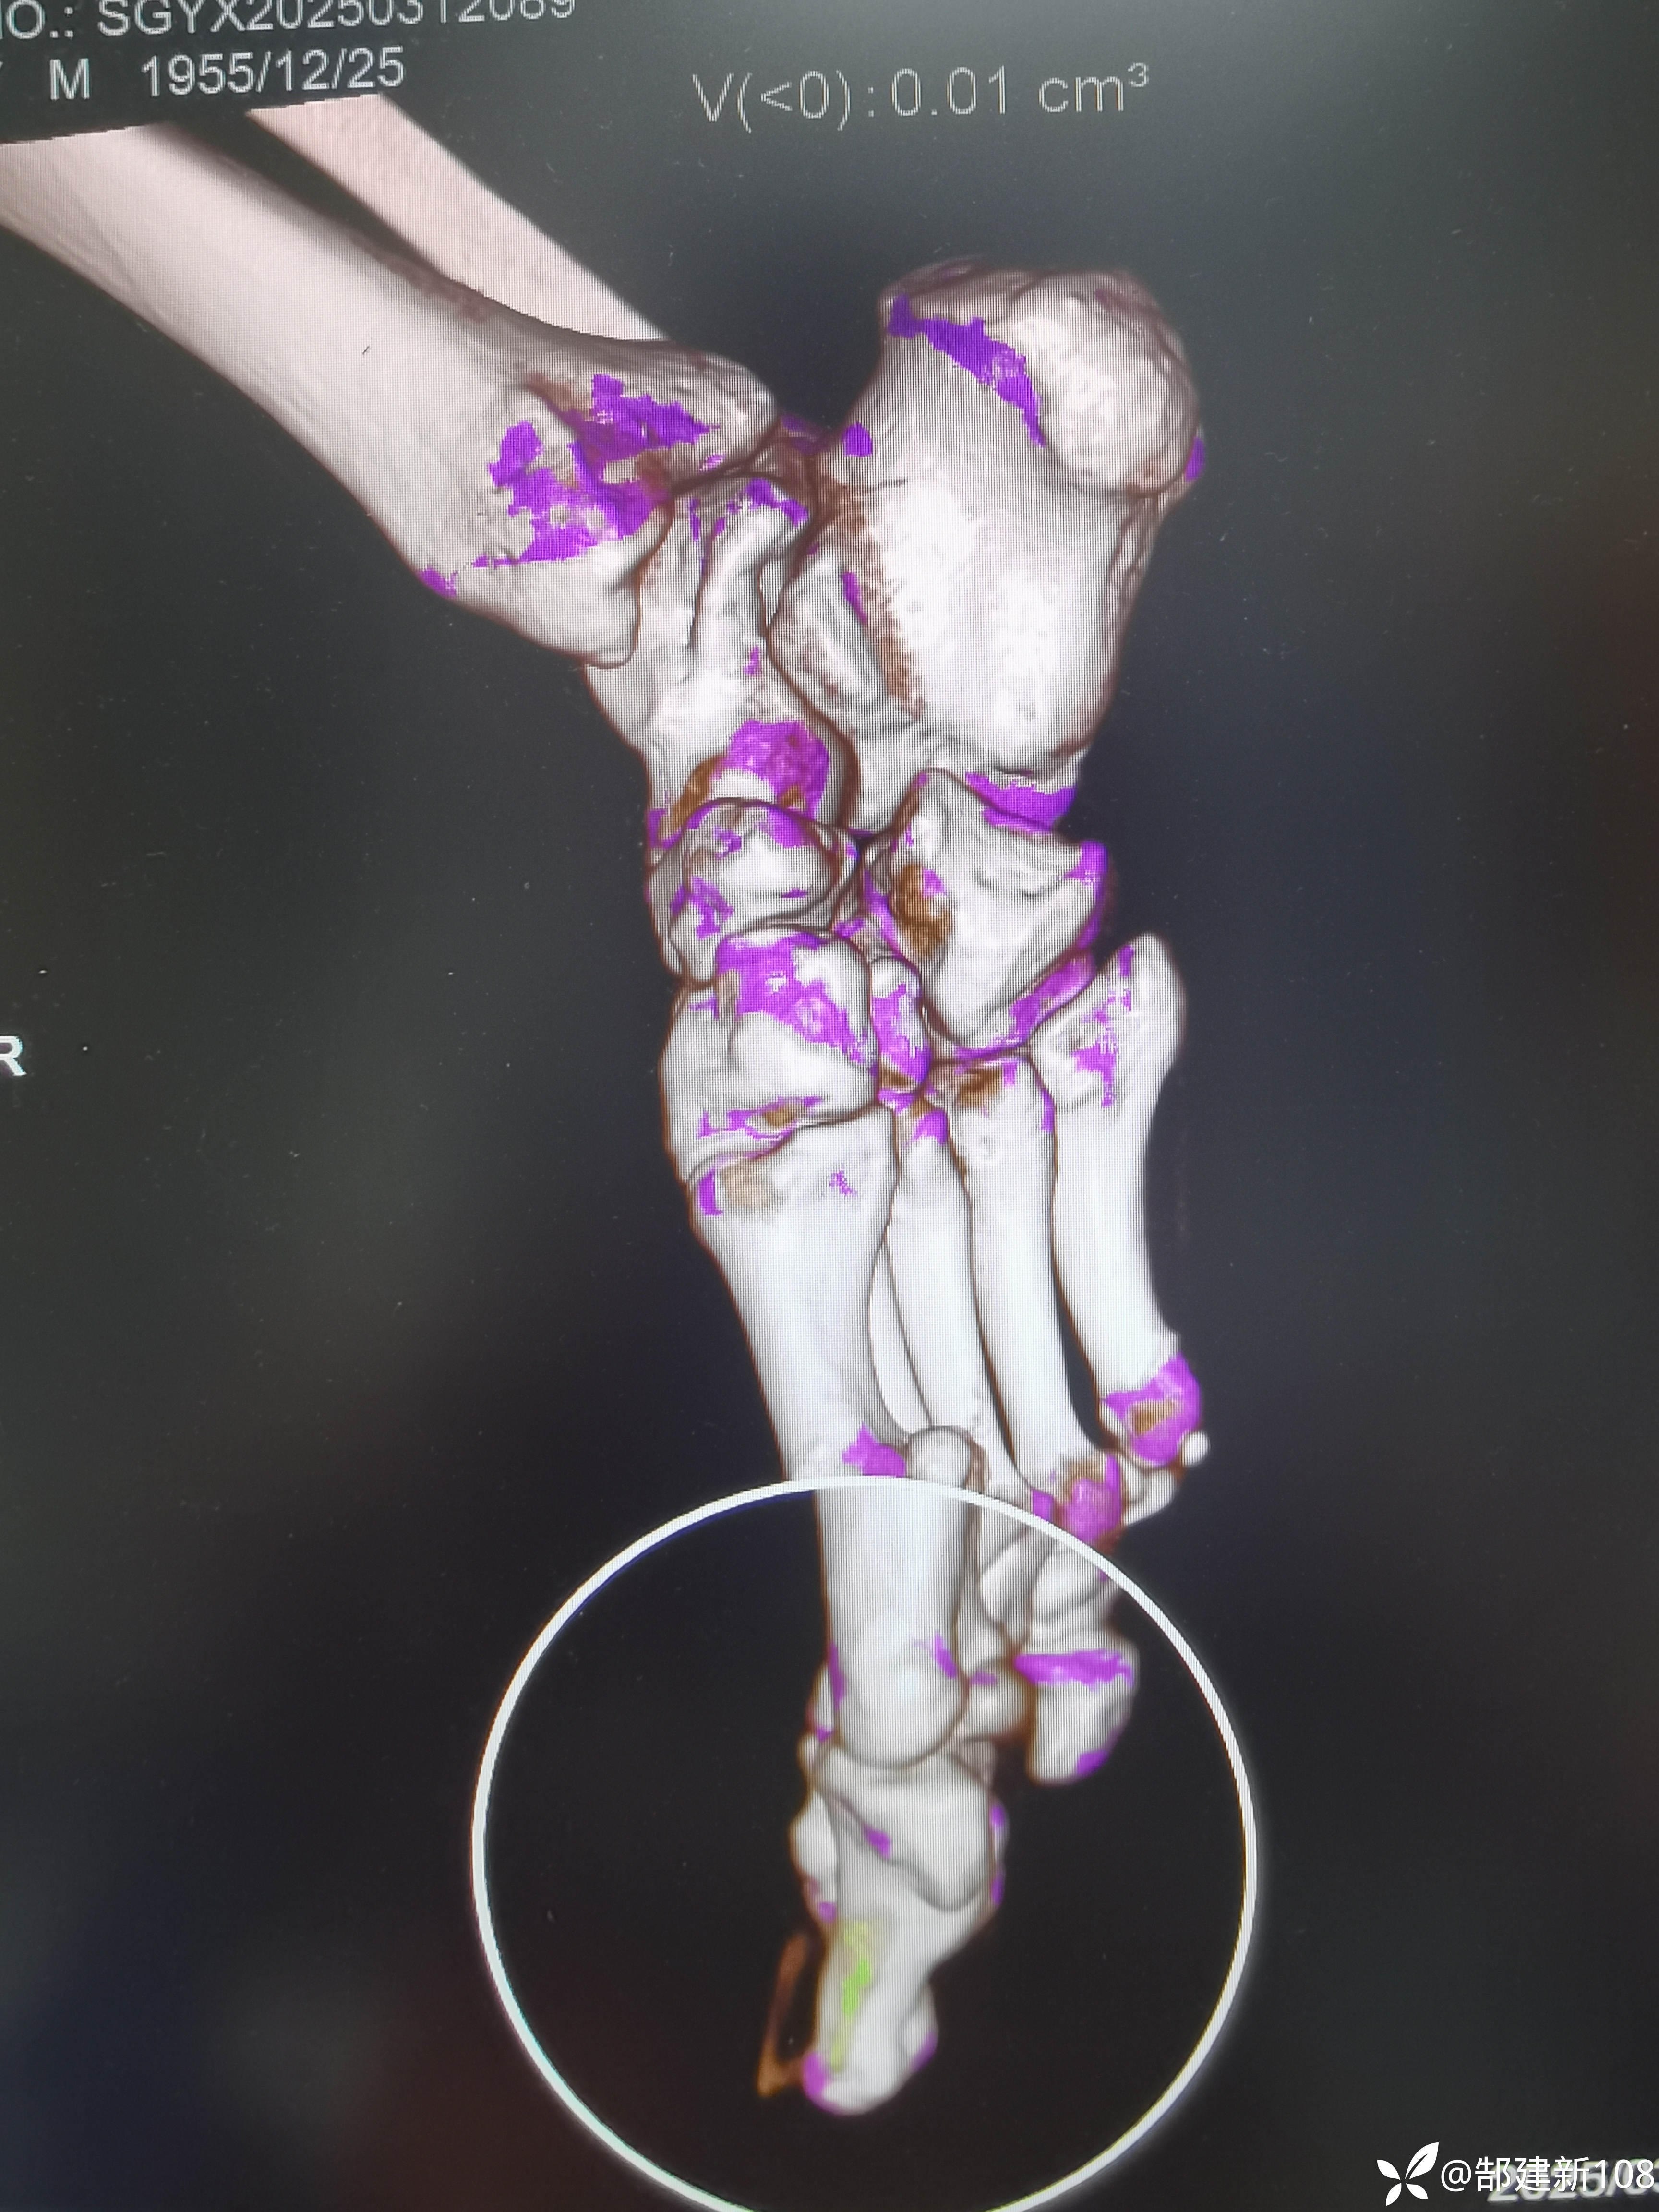

患者男,45岁,尿酸增高3年,足部发作疼痛3天。

筛查早期痛风石可以用双源CT来帮忙,能量成像伪彩色查到绿色的地方可以用读片放大镜或缩放功能可以发现小米粒大小的痛风石。